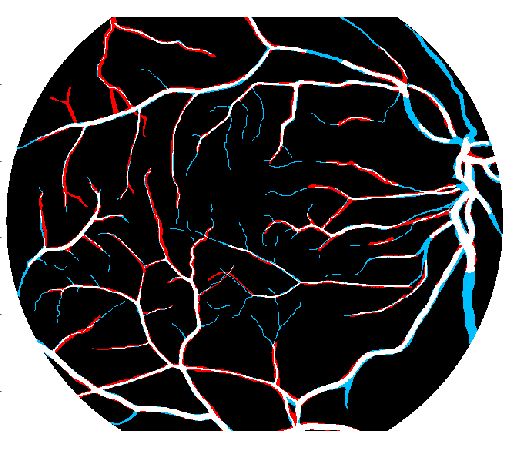

4.2 Validation of the Stationary Wavelet Transform

Having analyzed our Base System, we evaluate the effects of incorporating the SWT into it. The results of each variant are shown in Table 4, while the probabilistic predictions can be seen in Fig. 5. The patches coming from the SWT were concatenated in the input, by varying the total number of input channels. We resorted only to detail coefficients since the goal was to enhance image transitions. We started by concatenating the detail coefficients of the first level in the initial green channel input – BS + . Then, we added those of the second level – BS + + . Finally, only the latter were kept – BS + .

Analyzing the results of the tests performed, we notice that all the alternative strategies improved the performance of the Base System, in terms of Acc and AUC. This means that the use of features based on the wavelet decomposition, whose effectiveness for vessel segmentation is well-known (Soares et al.,, 2006; Zhang et al.,, 2017), is also beneficial when combined with a deep learning methodology. In particular, we see that the first level SWT coefficients used on BS + were less effective than those of the second level applied on BS + . The first level translates spectral information of higher frequencies; this seems to have induced more false positives, as can be seen in Fig. 5. On the other hand, the second level SWT coefficients introduced statistically significant differences to the Base System, in both Acc and AUC, which seems to reinforce the idea that even deep learning methods can benefit from domain knowledge. In fact, they allowed to reduce the combination of false positives and false negatives as we can see in Fig. 5 as well. From now on, we will refer to the best model (BS + ) as Proposed.